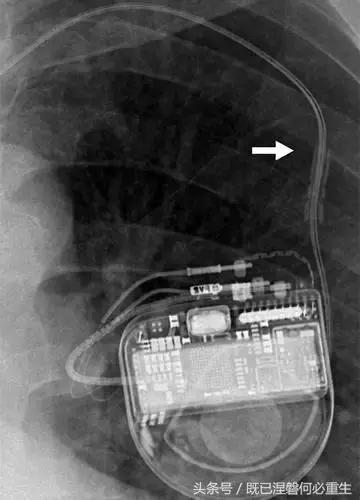

用于将导线的近端部分固定到胸壁的导线固定件可以模拟损伤。扎带是通常位于锁骨和发生器之间并且可以压接引线的套囊(图8A和8B)。熟悉这种外观和通常的射线透射束缚的位置可以防止错误报告磨损的线索。

图。 8A在两个不同患者中电极断裂的电极结合物的实例。

图。 8B在两个不同患者中电极断裂的电极结合物的实例。